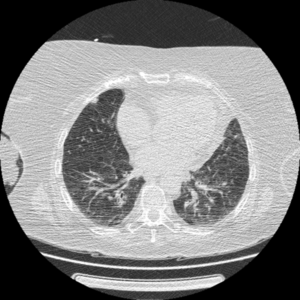

【EIRL Chest CTによる表示例】

(1) 標準線量CT